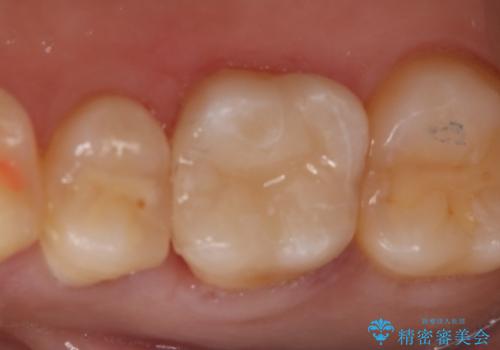

- 右上6番の虫歯治療を主訴に来院された患者様です。

切削量・形態を考慮し、セラミックインレーでの治療を計画しました。

保険の材料が劣化し中で虫歯が進行していたので、全て取り除いた上で形を整え型をとりインレーをセットしています。